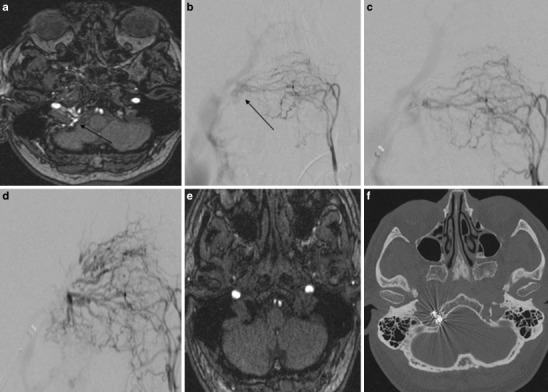

Fig. 5.

Case #3: a MR angiography source image from three-dimensional time-of-flight shows abnormal vascularization in the right hypoglossal canal compatible with a DAVF of the anterior condylar vein. b Anteroposterior (AP) view after injection of the left ascending pharyngeal artery shows a DAVF of the anterior condylar vein with a venous pouch located medially to the jugular bulb. c AP view after injection of the left ascending pharyngeal artery shows the microcatheter in the venous pouch and partial coil occlusion of the DAVF due to a transvenous approach. d AP view shows the complete occlusion of the DAVF; e MR angiography source image from three-dimensional time-of-flight shows no abnormal vascularization in the right hypoglossal canal anymore. f Axial computed tomography (CT) scan of the skull base shows the location of the coils in the right hypoglossal canal

Due to the reduced quality of life caused by the pulse-synchronous tinnitus the patient decided to undergo endovascular treatment.

Due to the high volume of the shunt we initially decided to perform the first treatment session transarterially over a 6Fr guide catheter that was placed in the ipsilateral external carotid artery. Multiple arterial feeders were then consecutively catheterized and occluded using N-Butyl Cyanoacrylate (NBCA) with marked reduction of the shunt. Due to the persistence of the debilitating tinnitus we decided to perform a transvenous embolization in a second treatment session.

The transvenous intervention was carried out through a transfemoral approach. A 6Fr guide catheter was tracked into the right internal jugular vein. A microcatheter was advanced to the point of the fistula at the ACV and 11 detachable coils were deployed in the ACV und ACC (Fig. 5c, d).

The post-interventional MRI scan confirmed the complete occlusion of the DAVF (Fig. 5e). A computed tomography (CT) scan of the skull base confirmed the location of the coils in the HC (Fig. 5f). The tinnitus disappeared immediately after the second treatment and the patient was discharged 3 days after the treatment.

The follow-up angiography 2 years after the treatment confirmed the persistent complete occlusion of the DAVF. The patient has also remained asymptomatic during the 2-year follow-up.